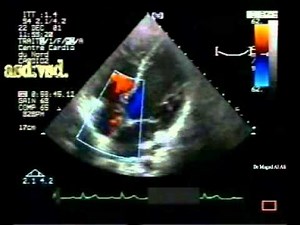

Combined Shunt: Septal Aneurysms, Atrial Septal Defect (ASD), Ventricular Septal Defect (VSD) • Video • MEDtube.net

medtube.net

Feb 2, 2015

Ostium Secundum ASD with LR Shunt

Atrial Caval Shunt

Bi-Directional Shunt